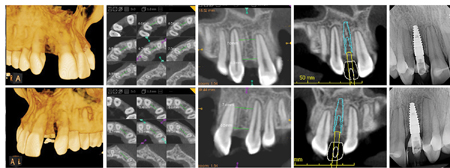

b) Adequate inter-radicular space

- When space is opened for a missing lateral incisor, the crowns of the maxillary central incisor and canines are tipped apart. The roots of these teeth do not move as quickly and often remain converged, possibly

obviating implant insertion. Therefore, additional attention and mechanics are important to make sure that the roots of the central incisor and canine are either parallel or slightly divergent.7,10,11,17,21,23,24 (Fig. 3) The root positioning must be evaluated prior to the removal of the orthodontic appliance through periapical radiographs,24 or CBCT. Communication with the surgeon is absolutely important at this time. - It is recommended that the distance between the head of the implant and the adjacent root be at least 1.5 mm to 2.0 mm,10,11 for preservation and proper development of the papilla.

- The ideal inter-radicular space should be at least 1mm1,26 to 1.5mm27 between the root and the implant. It bears noting that some patients with generally small teeth might be poor candidates for implant prosthesis due to current technological constraints i.e. implants are not as narrow as some naturally sized roots. In this situation an alternate restorative option could be considered.11

Fig. 3

The patient presented for orthodontic retreatment at 18 years old. She had previously been treated with spaces opened for the missing lateral incisors. (Figs. 5,6) During retention phase she struggled to use the retainers and consequently there was root relapse towards the edentulous area. The insertion of implants was not possible due to inadequate inter-radicular root position, this problem was exacerbated by her particularly small teeth. (Figs. 5,6) After a second round of orthodontic treatment featuring interproximal enamel reduction of the maxillary teeth, adequate radicular space and root parallelism was achieved for the implant insertion. (Figs. 7,8) The patient had bone grafting, implant placement and an excellent result was obtained. (Fig. 9)

Fig. 7

Fig. 8

Fig. 9